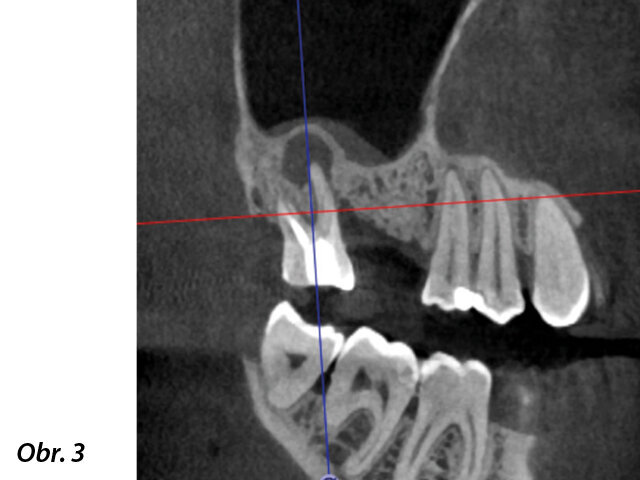

Klinický případ, kterým dále uvádím, je skvělým příkladem toho, jak obtížné je určit původ pacientových symptomů pouze na základě intraorálního snímku. Vizualizace 2D snímku selhává v jistotě určení přítomnosti léze, ještě důležitější však je, že je nemožné určit velikost, morfologii a typ léze, kterou se podaří nalézt. Analýza 3D snímku nám poskytne jasnou představu o klinické situaci: koronální a sagitální řezy odhalily přítomnost veliké léze sahající od apexu meziálního kořene tohoto moláru do furkace, zatímco axiální řezy nám umožňují provést přesnou analýzu endodontické anatomie a obzvláště pak tvaru meziálního kořene, který byl v tomto případě spojen s palatinálním kořenem. Celkový přehled o situaci ovlivňuje rozhodování o postupu a stanovení léčebného plánu zahrnujícího speciální úkony (obr. 1–4).